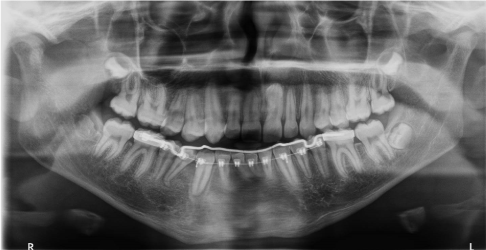

Marsupialization of the cystic lesion with avulsion of the deciduous elements involved in the lesion area is proposed, following which a lingual arch is applied to maintain the space for erupting teeth. After three and six months Ortopantomography was performed in order to check the evolution of the healing process and the eruption of the impacted tooth (Figures 7,8). Nine months from surgery 4.2 erupted and no cyst lesion was observed (Figure 9).

Figure 7 Case 2. Three months after marsupialization

Figure 8 Case 2. Six months after marsupialization.

Figure 9 Case 2. After nine months  there is no cystic lesion and the element displaced are erupted

Figure 6 Case 2. Initial ortopantomography